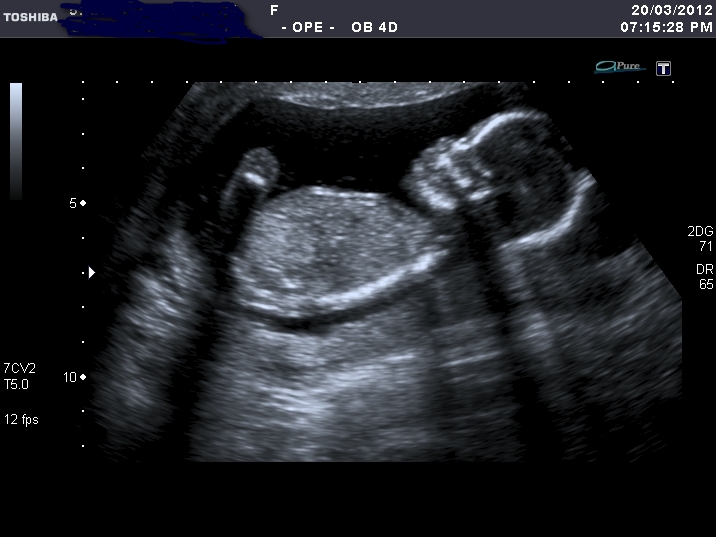

Yesterday I've had my u/s, baby looks perfectly healthy ( huge relief), but the tech was pretty sure it's a girl. I faked a happy face :worry: I'm 15weeks 5 days.